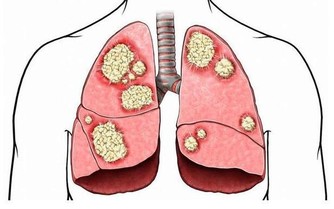

而很多人不知道的是,腳上有很多經絡通向肝臟,通過觀察腳上的變化就能判斷肝臟的健康狀況。

正常健康腳掌顏色應是白裡透紅,如果腳掌發白,無血色,可能是血液垃圾過多,致使血管淤堵,供給腳掌的血液不夠,腳掌自然呈現出發白的症狀,出現這種情況且伴有頭暈、眼花、無力等症狀時,應留意肝臟健康。

中醫學認為,正常腳底顏色略紅。排除一些角質層較厚的人會出現腳底發黃之外,還可能與肝臟有關係,當肝細胞破壞,使得血中的膽紅素不能正常的排除,逆流至血液中,呈現出腳底發黃。

很多人認為,腳底乾燥是因為腳部皮膚疾病而導致的,殊不知腳底肌膚與身體內分泌有關,當肝細胞受損時,可能影響身體內分泌正常,進而導致皮膚暗黃、腳底變得乾燥,常出現脫皮、乾裂情況,這些情況應留意是否是肝臟受損。